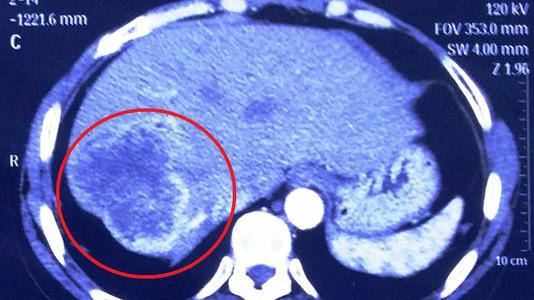

摘要:目的分析隐匿性胆囊癌的病理学特点。方法从2016年1月至2018年12月我院腹腔镜手术切除胆囊的患者中,选取术后被诊断为隐匿性胆囊癌的患者50例进行研究,分析隐匿性胆囊癌病理学特点。结果术前腹部B超检查,所有患者均患有胆囊炎,显示胆囊大小正常的9例,胆囊壁轻度增厚41例,其中10例出现胆囊扩增,7例合并胆囊息肉。其中伴有胆囊结石、伴有胆管结石分别有29例、4例,2例患者行薄层CT扫描出现胆囊壁不规则增厚;发病部位在胆囊颈部、体部、底部分别有5例、30例、15例;肉眼观察有15例胆囊大小与正常大小胆囊无明显差异。

发现胆囊增大,囊壁不均病例有23例,胆囊壁厚0.5-1.7 cm,平均(0.89±0.12)cm,有3例表现为息肉样,有10例病例可见胆囊呈囊性增大;在显微镜下,有30例为浸润性癌;普通型腺癌38例、乳头状腺癌10例、粘液腺癌1例、鳞状细胞癌1例;单纯黏膜内癌2例,呈乳头状生长,囊内乳头状肿瘤伴浸润性癌有8例,肿瘤细胞呈乳头状生长。结论隐匿性胆囊癌大多数伴有胆囊结石,肉眼观病变局限,主要组织学类型为腺癌、伴有浸润囊内乳头状肿瘤次之。

2.1影像学特点。术前,对所有患者行腹部B超检查,显示所有患者均患有胆囊炎,显示胆囊大小正常的9例,胆囊壁轻度增厚41例,其中10例出现胆囊扩增,7例合并胆囊息肉。其中伴有胆囊结石、伴有胆管结石分别有29例、4例,2例患者行薄层CT扫描出现胆囊壁不规则增厚。

2.2病理学检查。根据病理学检查发现,患者发病部位在胆囊颈部、体部、底部分别有5例、30例、15例。肉眼观察与正常胆囊大小无明显差异的患者有15例,胆囊壁类似正常胆囊。发现23例患者胆囊增大,囊壁不均,胆囊壁厚0.5-1.7(0.89±0.12)cm,增厚区范围不一,切面质地韧、呈灰白色。有3例表现为息肉样,边界不清、呈孤立性生长。有10例病例可见胆囊呈囊性增大,黏膜粗糙,呈乳头状。

在显微镜下,有30例为浸润性癌,占大多数,肿瘤细胞在胆囊壁内呈浸润性生长,胆囊壁广泛增厚变硬,切面灰白色,也可或易见神经侵犯,且少数病例出现促纤维增生反应;以粘膜内癌为主,单纯黏膜内癌2例,呈乳头状生长,腺体异型性明显,可累及正常腺体;囊内乳头状肿瘤伴浸润性癌有8例,呈乳头状生长,形成复杂乳头结构,细胞有异型性呈高级别上皮内瘤变,易见核分裂,肌层或全层内可见异型腺体浸润。组织学类型上可见普通型腺癌、乳头状腺癌、粘液腺癌、鳞状细胞癌分别有38例、10例、1例、1例。